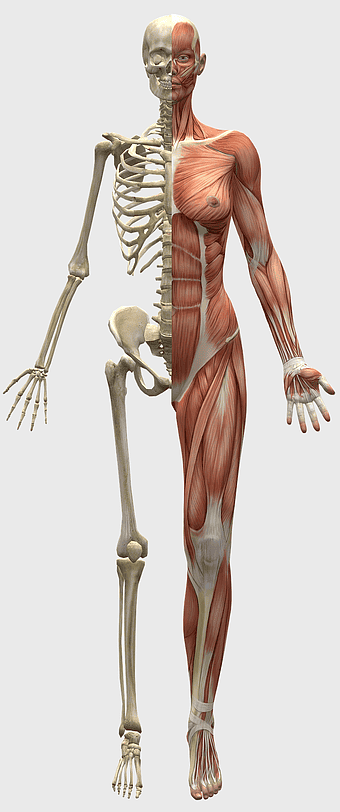

female human organ model, human digestive system anatomy, gastrointestinal tract illustration, liver and stomach diagram, medical education visuals, anatomical study aids, human body internal structures -

female anatomy diagram, human organ system chart, woman's body structure, female internal organs, human anatomy illustration, medical educational image, anatomical reference guide -

Breast cancer, musculoskeletal system, human anatomy, health care, skeletal muscle structure, medical illustration, body composition analysis -